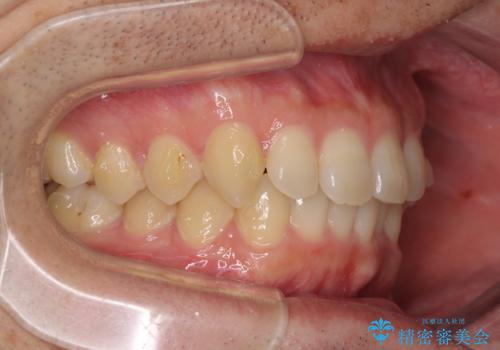

- 上下前歯のデコボコと深い咬み合わせを気にして来院された患者様です。

インビザラインによる上下歯列の拡大と、IPR(歯と歯の間を削る)にるスペースの獲得により、前歯のデコボコとディープバイトを改善することとしました。

もう少し下の前歯を整えたかったのですが、患者様の治療を早く終了させたいという希望により、細かい叢生を残しての終了となりました。